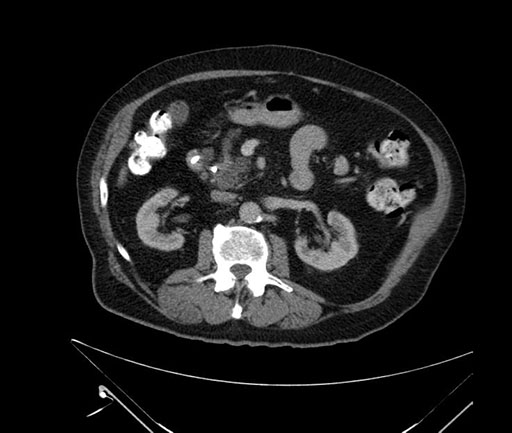

Imaging Analysis

Look through the patient's CT scan to identify any areas of concern for the necessary procedure.

Based on your CT findings, which issue(s) would give reason for "planned slowing down moment(s)" in this case?